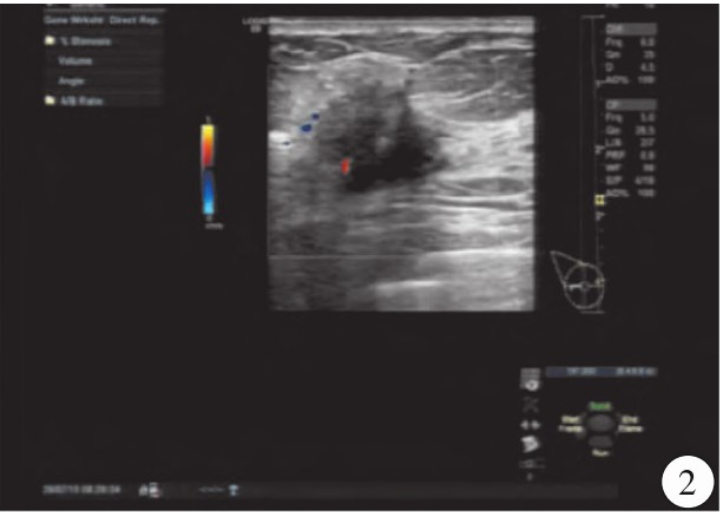

超声检查:右乳腺见大小约3.0cm×1.8 cm×2.4 cm的低回声结节,边界不清,形态不规则,呈角样改变,内见微钙化,弹性成像组织显示蓝色(图1),CDFI显示右乳腺低回声结节内见星点样血流信号(图2);右侧腋窝见约1.4cm×1.1 cm的淋巴结,门结构显示不清,右侧腋窝淋巴结内均见少许星点样血流信号(图3),诊断右乳腺BI-RADS 4c类结节,右侧腋窝异常肿大淋巴结。MRI显示右乳腺外上象限可见结节样稍长T1、稍短T2结节影,边界不清,呈毛刺状,病灶大小约2.1 cm×2.5 cm×2.1 cm,增强扫描呈环形强化(图4、5)。

图4、5 MRI显示右乳腺外上象限可见结节样稍长T1、稍短T2结节影,边界不清,呈毛刺状。

本例患者以乳腺包块就诊,超声检查显示右乳腺结节形态不规则,其内见微钙化,CDFI显示右乳腺低回声结节见星点样血流信号,右乳腺BI-RADS 4c类结节。MRI显示右乳腺结节,呈分叶状,增强后呈环形强化,时间-信号曲线呈流出型,右乳腺BI-RADS 4c类结节。